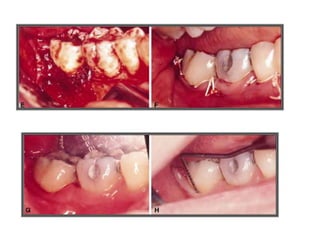

TRATAMENTO DAS LESÕES

ENDOPERIODONTAIS

Rizectomia

DEL RIO, 1996

Rizectomia